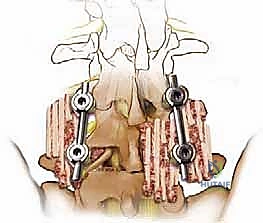

تقنية PLIF (الاندماج الفقري القطني الخلفي)

في هذه التقنية، يتم الوصول إلى العمود الفقري من الخلف مباشرة. يقوم الجراح بإزالة جزء من العظم (الصفيحة الفقرية Laminectomy) للوصول إلى القناة الشوكية. يتم سحب الأعصاب برفق إلى الجانبين للوصول إلى القرص التالف وإزالته، ثم يتم إدخال "أقفاص" (Cages) مدعومة بطعوم عظمية من كلا الجانبين.

* الميزة: تتيح رؤية ممتازة للقناة الشوكية وإزالة شاملة للضغط من الجانبين.

تقنية TLIF (الاندماج الفقري القطني عبر الثقب)

تُعد TLIF تطوراً لتقنية PLIF. بدلاً من الدخول مباشرة من المنتصف وسحب الأعصاب بشكل كبير، يتم الوصول إلى القرص الغضروفي من جانب واحد عبر "الثقبة" (Foramen) - وهي الفتحة التي يخرج منها العصب.

* الميزة: تتطلب سحباً أقل بكثير للأعصاب الشوكية، مما يقلل من خطر الإصابة العصبية ويقلل من تندب الأنسجة، وغالباً ما تتم عبر شقوق جراحية أصغر.

الخطوة 4: زراعة القفص والطعم العظمي (Cage Insertion)

يتم إدخال قفص مصنوع من مادة PEEK أو التيتانيوم، مملوء بطعم عظمي (يؤخذ غالباً من المريض نفسه أو طعم صناعي)، في المساحة الفارغة. هذا القفص يعيد الارتفاع الطبيعي للفقرات ويخفف الضغط عن منافذ الأعصاب.